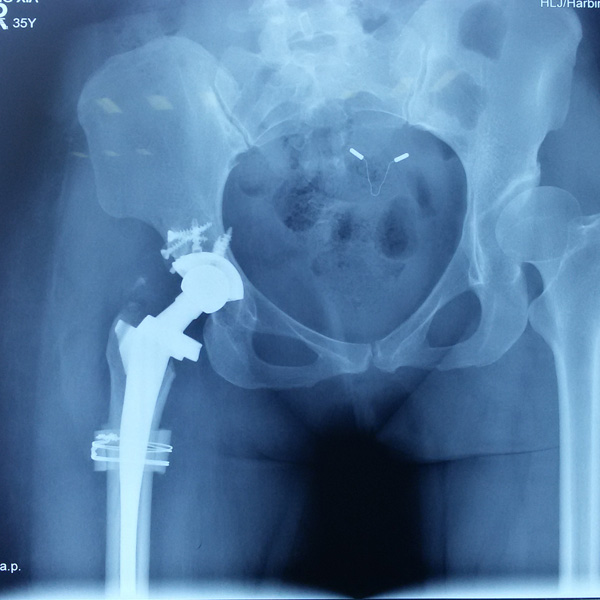

• 先天性髖關節脫位先天性髖關節脫位手術后手術前

先天性髖關節脫位

患者王某某,女,41歲,從會走路以來就發現一條腿長,一條腿短,也就是人們俗稱的“跛子”,之前雖然兩條腿長短不一,但起碼還可以走路,維......